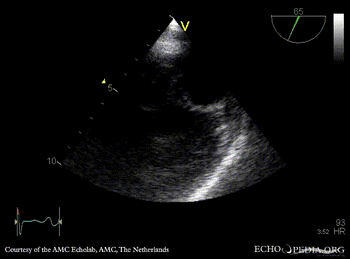

Flail of mitral valve

PLAX: flail of mitral valve PLAX: prolaps of PMVL